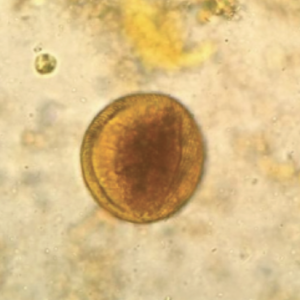

En este Atlas encontrarás una recopilación de los principales protozoos parásitos y comensales, así como de los principales helmintos que se alojan en el tubo digestivo humano. Incluyendo una descripción detallada sobre la morfología característica de cada organismo que conlleve a su rápida identificación.